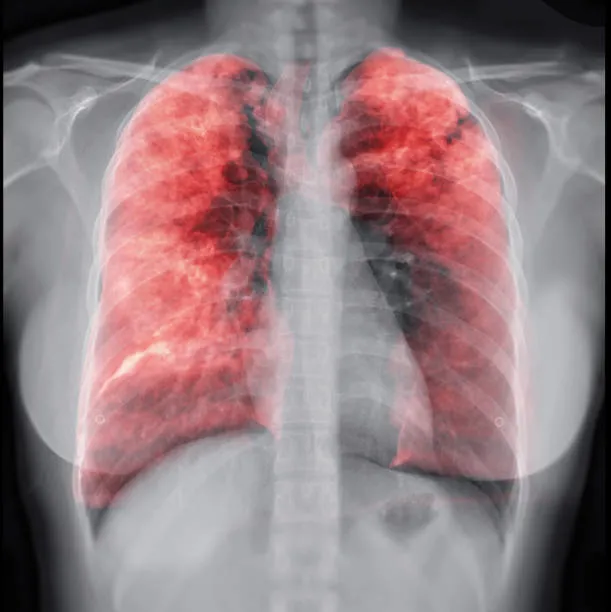

Akciğer kanserinin belirtileri, günlük yaşamda sıkça karşılaşılan diğer sağlık sorunlarına benzer olduğu için genellikle ihmal edilebilir.

Diğer akciğer kanseri belirtileri arasında geçmeyen veya şiddetlenen öksürük, göğüs ağrısı, iştahsızlık, yorgunluk, halsizlik, kilo kaybı, ses kısıklığı ve nefes darlığı bulunur.

Ayrıca, sürekli tekrarlayan bronşit veya zatürre gibi akciğer enfeksiyonları da akciğer kanserinin belirtileri arasında yer alabilir.